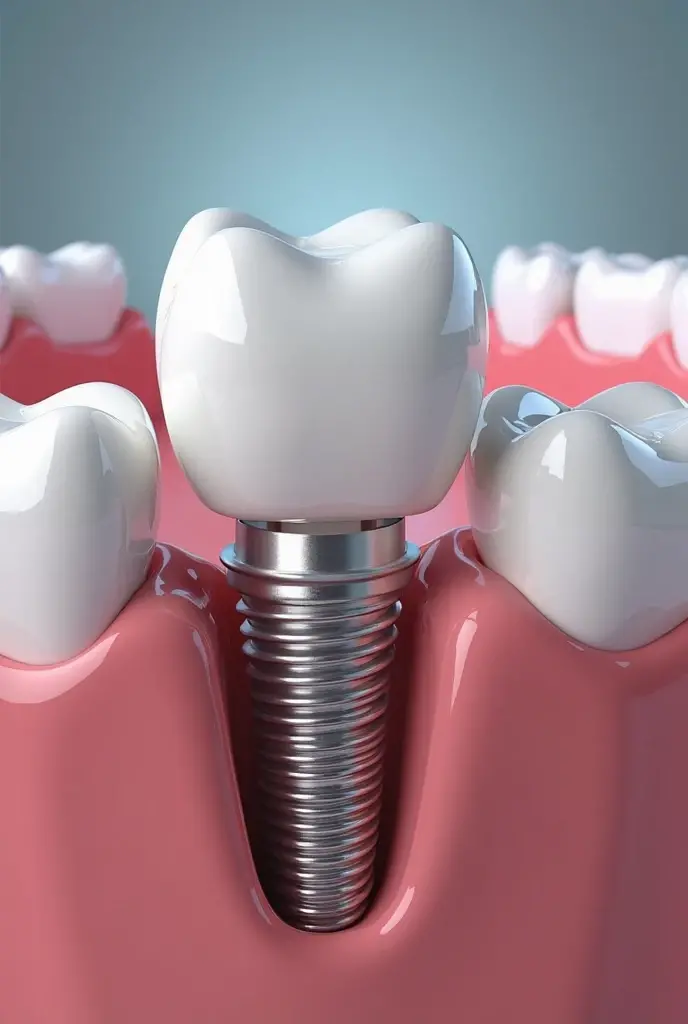

Create an artistic image that reimagines a dental implant as a luxurious work of art. The implant should be central in the composition, with intricate details that highlight its structure, such as the titanium post and the crown, all rendered in a refined and elegant manner. Surround the implant with artistic elements like flowing gold accents, delicate textures, and subtle patterns that evoke a sense of luxury and precision. The background can be minimalist, using soft gradients or abstract forms to keep the focus on the implant while enhancing the overall aesthetic. The image should blend the technical precision of a dental implant with the elegance and sophistication of fine art, creating a piece that is both visually striking and conceptually unique

Create an artistic image that reimagines a dental implant as a luxurious work of art

such as the titanium post and the crown